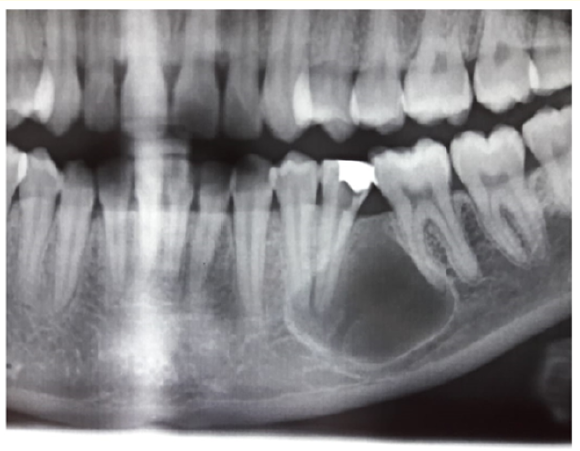

Glandular Odontogenic Cyst: Report of Two Cases

Eldhose KG, Paul Steaphen and Anu Jose. 6(4): 149-154.